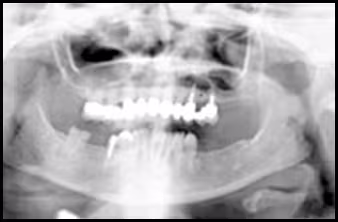

These figures demonstrate the effects of positioning the head too far down.

Figure 48A. Panoramic Image.

Figure 48B. Panoramic Schematic.